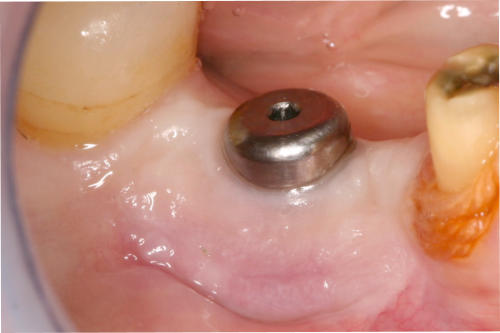

Gingivatransplantat fixiert